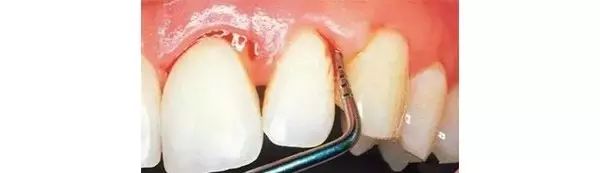

第一步:浅龋

当我们身上有小黑点时,您毫不在意地说:“没事的,没感觉。”

牙医说:“龋病是由以细菌为主的多因素导致的牙齿硬组织发生慢性进行性破坏的一种疾病。已经开始浅龋即牙釉质龋,需要做药物治疗或充填治疗